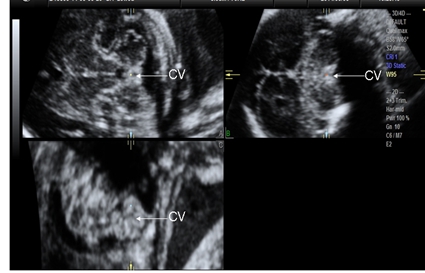

超声评估胎儿小脑蚓部发育是产前筛查胎儿神经系统的重要部分,临床上以小脑蚓部发育异常为特征的疾病主要有Dandy-Walker畸形(Dandy-Walker malformation,DWM)、Dandy-Walker 变异(Dandy-Walker variant,DWV)和Blake 囊肿(Blake′ s pouch cyst,BPC)。这几类异常在超声表现上有相似之处,二维超声横切面上都表现为第四脑室扩张和后颅窝池相通,但预后差异很大。近年来国内外多位学者应用三维超声获得胎儿小脑蚓部正中矢状切面评价胎儿小脑蚓部发育是否正常,通过观察胎儿小脑蚓部的形态、结构及测量小脑蚓部面积等方法对上述疾病进行诊断和鉴别诊断,取得了一定的成果。在颅脑正中矢状切面上,脑干小脑蚓部(brainstem-vermis,BV)角、脑干小脑幕(brainstem-tentorium,BT)角作为分析小脑蚓部和脑干的关系、小脑幕插入角度的定量指标,也开始逐渐应用于评价胎儿小脑蚓部发育的研究。

注:CV为小脑蚓部 图1 经腹三维超声显示正常胎儿小脑蚓部三个正交平面声像图

注:tentorium为小脑幕;CV为小脑蚓部;FV为第四脑室;CC为胼胝体;CSP为透明隔腔;TV为第三脑室;BS为脑干; 图2 经腹三维超声C平面显示正常胎儿小脑蚓部正中矢状切面声像图

本研究选择2013年7月至2014年7月在南京医科大学附属苏州市立医院产前超声中心接受系统超声检查未发现明显异常,追踪至分娩后无明显异常的单胎妊娠胎儿335例(正常组)。结果显示BV角测值为1.0~10.0°,平均测值为(3.3±1.7°);BT角测值为16.6~57.8°,平均测值为(31.5± 6.9°)。在整个孕期变化不大,与孕周无明显相关性,可作为定量衡量脑干上方小脑蚓部旋转角度和小脑幕插入角度简单、可重复性检查的参数。

选择同期超声诊断为小脑蚓部发育异常并经胎儿磁共振成像证实与超声诊断相符的胎儿16例(小脑蚓部异常组)。16例小脑蚓部发育异常胎儿中4例Dandy-Walker畸形胎儿小脑蚓部受压明显上抬,BV角测值明显增大为62.7~104.5°,平均为(88.9±18.1°),小脑幕上抬,BT角测值明显增大为74.3~103.4°,平均为(89.0±12.8°);6例Dandy-Walker变异胎儿小脑蚓部上旋,BV角测值增大为18.4~31.1°,平均为(23.7±5.2°),BT角测值稍增大为42.9~71.7°,平均为(54.5±12.0°);6例Blake囊肿胎儿小脑蚓部上旋,BV角测值轻度增大为13.9~18.5°,平均为(16.7±1.8°),BT角测值为42.7~61.2°,平均为(50.3±8.2°)。

胎儿小脑蚓部正中矢状切面BV角和BT角的测量可直观显示小脑蚓部发育异常组胎儿小脑蚓部上旋和小脑幕上抬的程度。Blake囊肿、Dandy-Walker变异、Dandy-Walker畸形3类病例中的BV角均大于正常组胎儿的BV角,且随着小脑蚓部发育异常程度的增加而增加。Dandy-Walker畸形胎儿的BV角>60.0°,Blake 囊肿中BV角>10.0°但<20.0°,Dandy-Walker变异胎儿的BV角位于中间。BV角的定量测量在一定程度上可对伴有蚓部上旋的蚓部发育异常的病例进行鉴别诊断。BT角在小脑蚓部异常组胎儿中也会增大,尤其在Dandy-Walker畸形病例中,小脑幕受压明显上抬,BT角明显增大。但在其他2类疾病中,BT角的测量值会有重叠,限制了其在这2组疾病中的鉴别诊断价值。